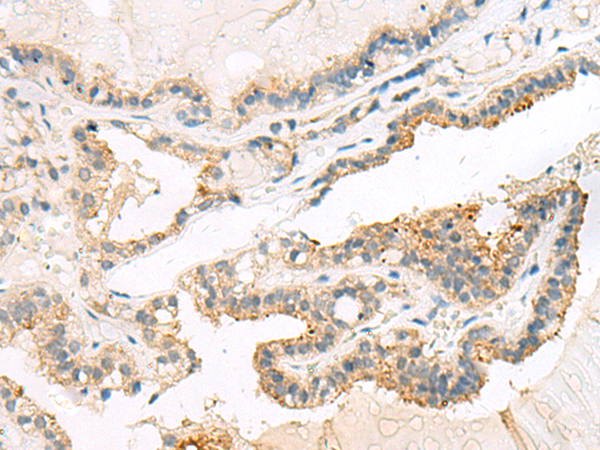

IHC positive control: |

Human liver cancer and Human thyroid cancer |

IHC Recommend dilution: |

20-100 |